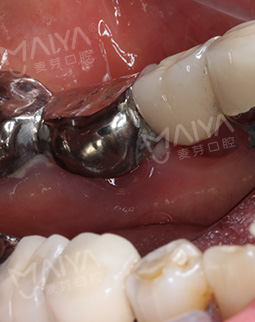

为了确保种植手术的安全性,在种植术前,麦芽口腔宝安机构赵旭峰院长为肖阿姨做了全面检查,考虑到肖阿姨年龄大,又缺牙久,牙槽骨萎缩已经很严重。如果采用传统的种牙方法,不仅需要大量植骨,植骨后还需等待牙槽骨恢复,这将大大增加种植的时间。再三思索后,赵院长决定采用麦芽MAC数字化精确种植技术,这样仅需个别牙齿先植骨,再通过数字化导航技术精确植入植体就可恢复上半口牙齿。"来麦芽口腔果然没有错,年龄这么大,本来还担心能不能种,赵院长给我吃了一颗定心丸。"听完赵院长对方案的讲解后,肖阿姨心头的一块巨石终于落了下来。